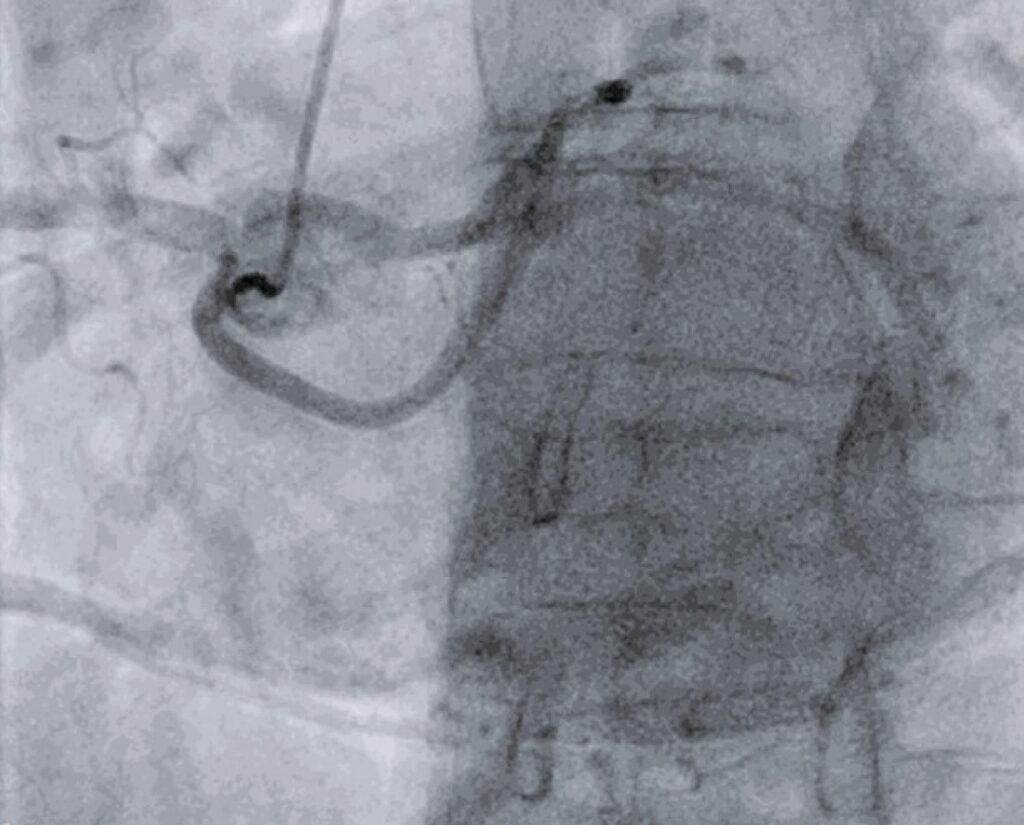

A 61-year-old female patient was referred to the cardiology department for dyspnea upon exertion. A transthoracic echocardiogram showed a severely stenotic bicuspid aortic valve and normal ejection fraction in both ventricles. She was submitted to a routine preoperative coronary angiography. A right radial access was obtained. Despite numerous efforts, it was not possible to visualize the origin of the left main coronary artery at the left ostium. Catheterization of right coronary artery was done and demonstrated a normal implantation at the right sinus. Surprisingly, the left anterior descending artery (LAD) as well as the left circumflex artery (LCx) ostia were found at the right sinus, and were separated with an absent left main coronary artery. No other abnormalities were found on angiography.